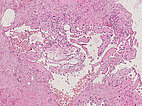

Hematoxylin & eosin stain, 21× magnification: A phlebolith already transformed into connective tissue is shown top right. Overall, as an indication of a vascular lesion, increased irregular vascular cavities are visible in the histopathological overview image.